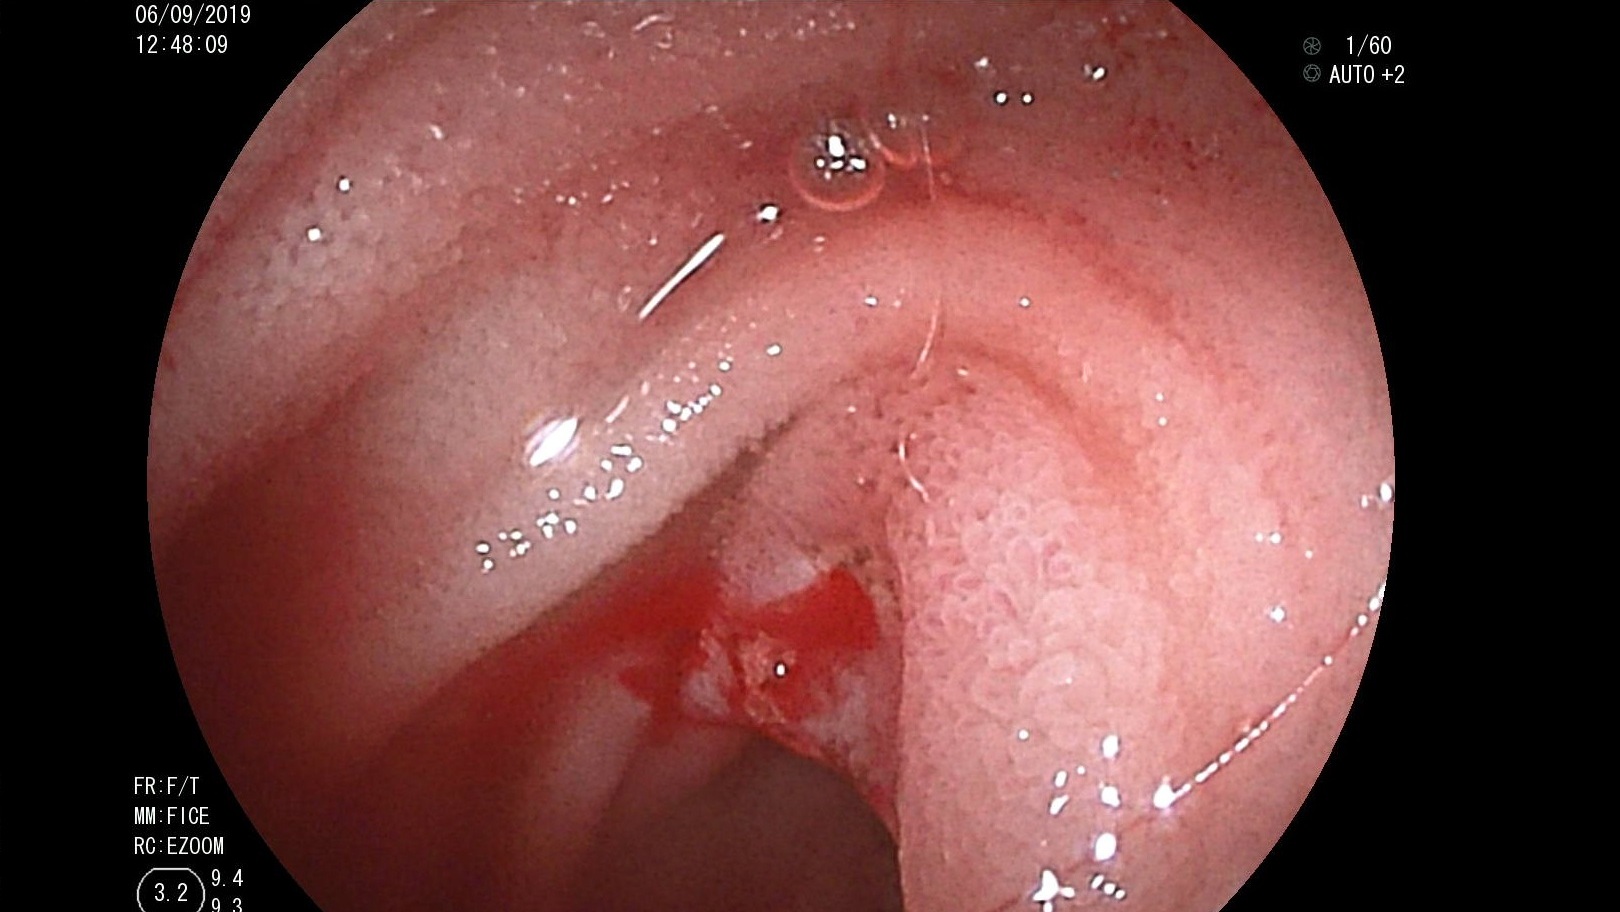

Can thiệp nội mạch cấp cứu một trường hợp vỡ túi giả phình động mạch lách ở bệnh nhân viêm tụy mạn tại Bệnh viện Trường Đại học Y Dược Huế

Bệnh nhân Hoàng Lương T, nam 67 tuổi, được chuyển đến Bệnh viện Đại học Y Dược Huế ngày 15/10/2019 với triệu chứng đi cầu phân đen đã hơn 1 tháng. Bệnh...